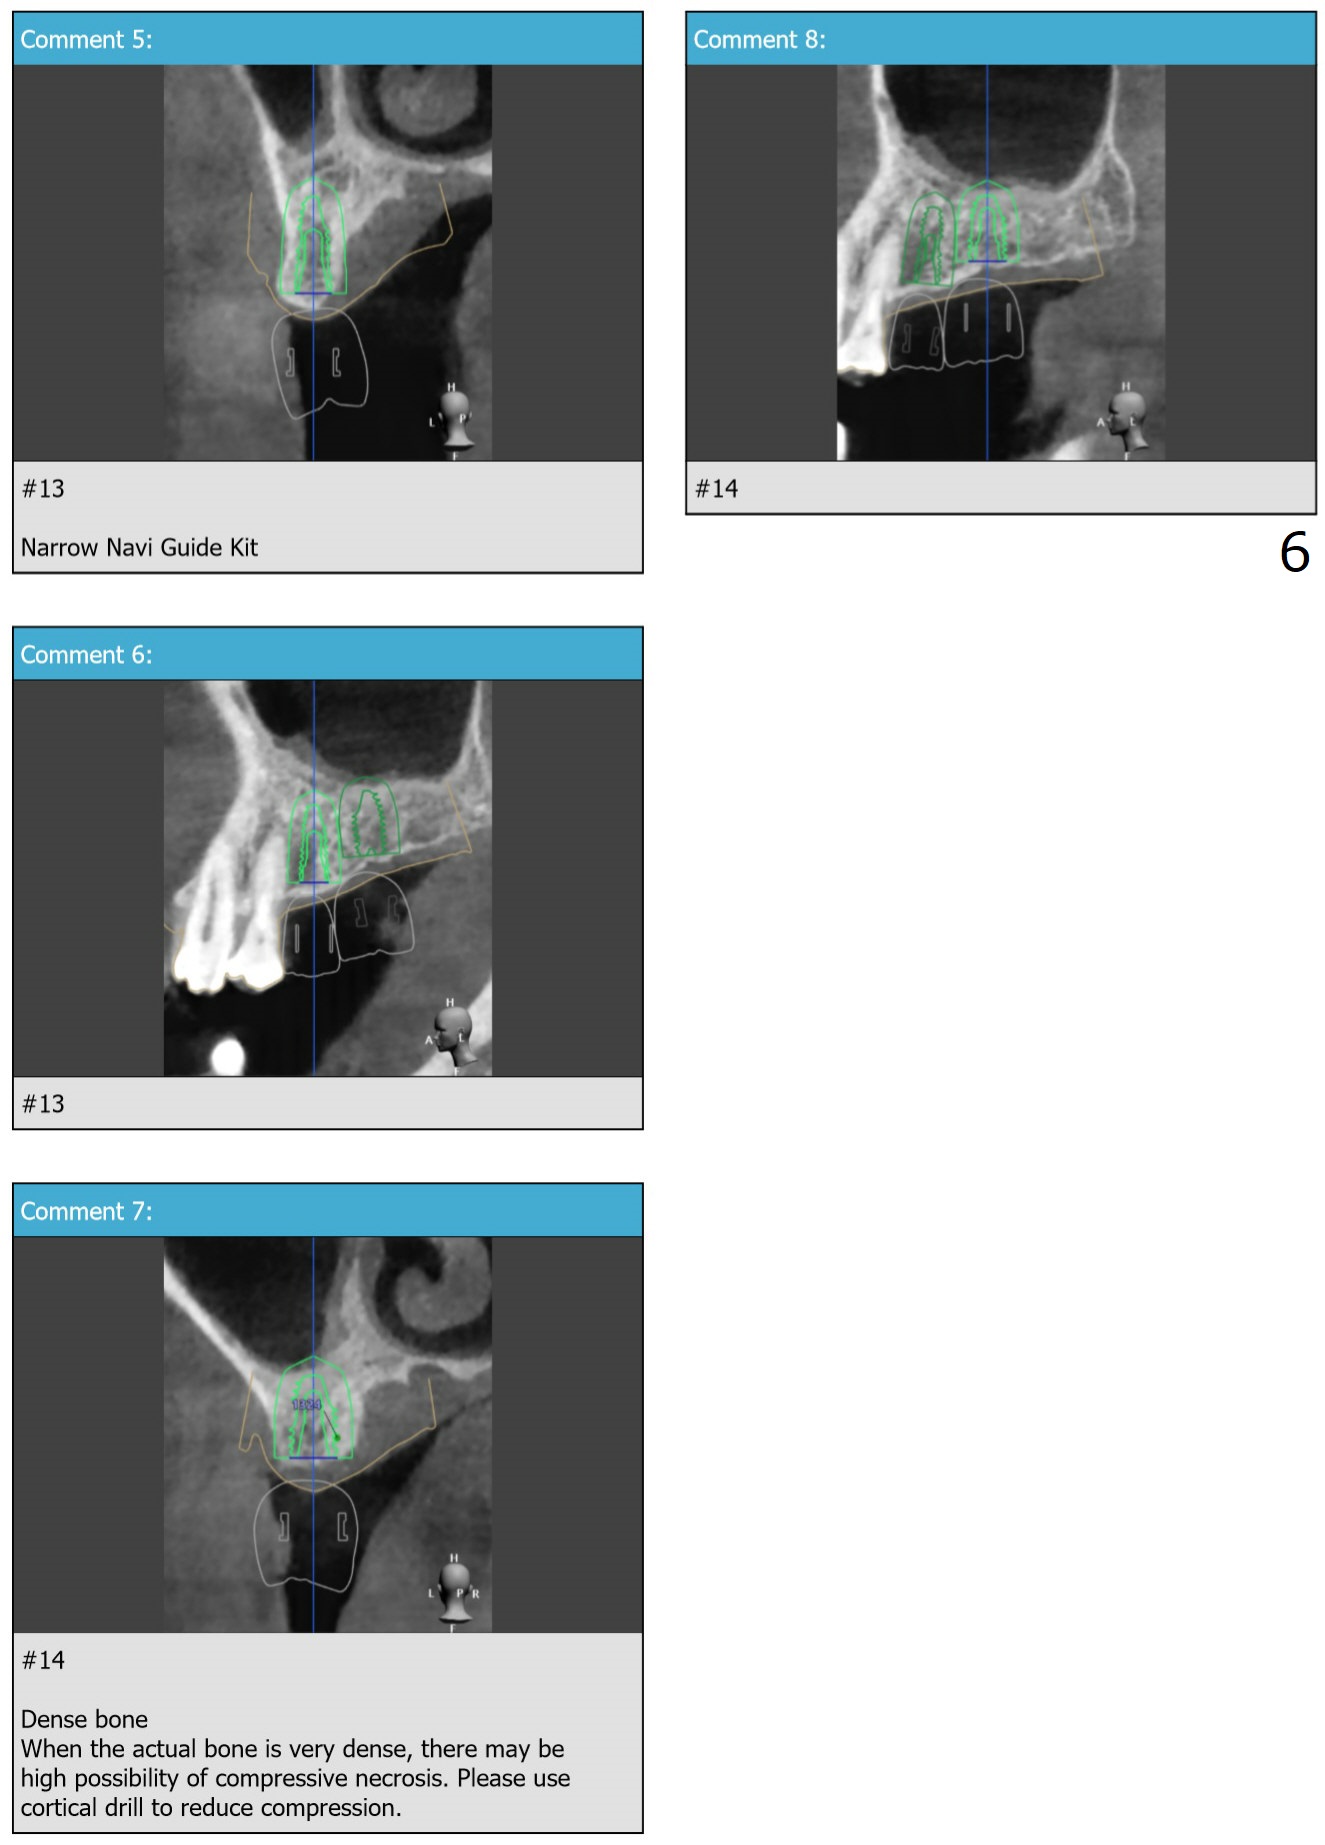

Compressive Necrosis

Return to No Deviation 矫正,糖尿病,种植水平

Xin Wei, DDS, PhD, MS 1st edition 03/19/2020, last revision 12/06/2020